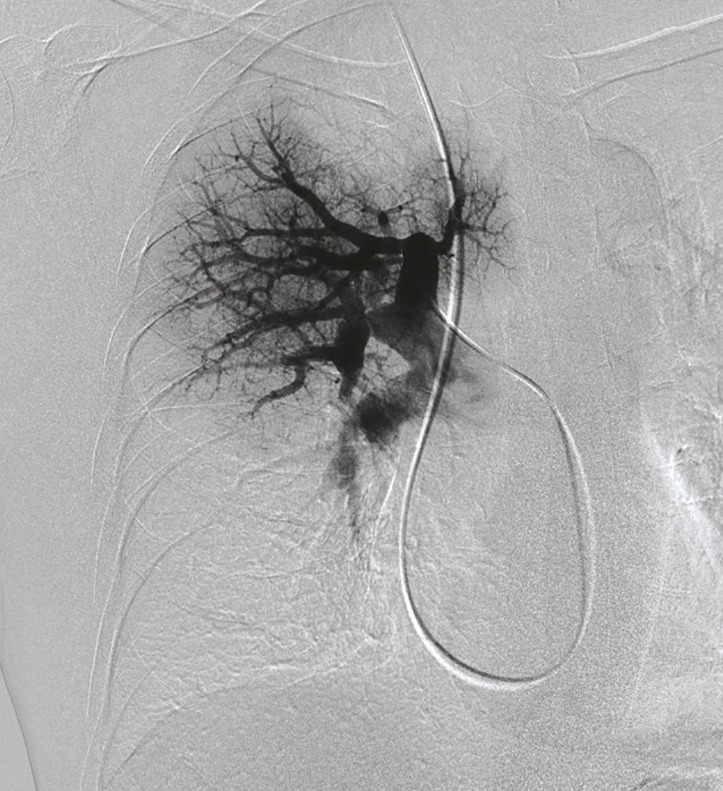

Monsieur M. est adressé par son cardiologue dans un centre de compétence en hypertension pulmonaire. Le cathétérisme cardiaque droit confirme le diag- nostic d’hypertension pulmonaire précapillaire avec une PAPm à 73 mmHg et une PAPo à 12 mmHg. La scintigraphie pulmonaire objective de multiples défects perfusionnels segmentaires et sous-segmentaires bilatéraux sans anomalie ventilatoire en regard (fig. 5).

La prise en charge de l’hyper- tension pulmonaire thrombo- embolique chronique dépend de la localisation des séquelles thromboemboliques, proximale ou distale. Deux examens sont utiles à ce stade, l’angio-TDM thoracique (fig. 6) et l’angiographie pulmonaire (fig. 7).